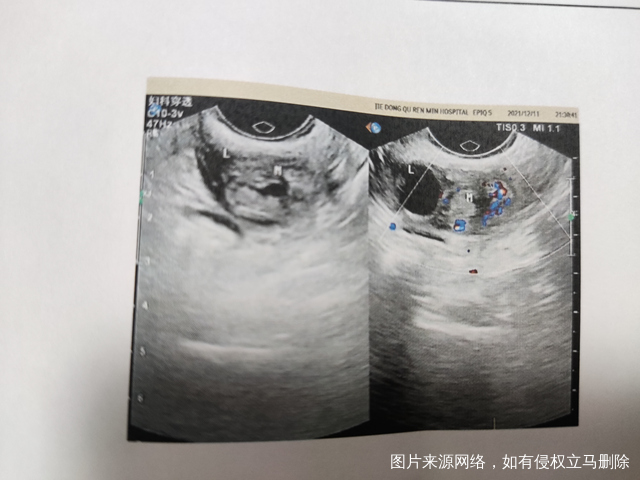

医生好我被诊断为宫外孕目前hcg为500多b